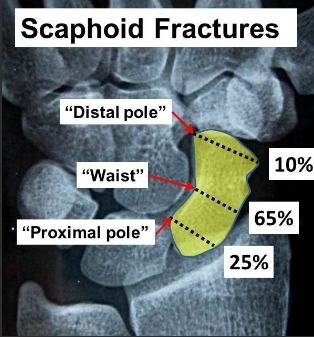

2. 주상골 골절의 분류

- 주상골 골절은 골절의 위치에 따라 대략적으로 근위부, 요부(허리, 중간), 원위부 골절로 나누며, 그 치료 방법과 예후가 달라지게됩니다.

- 근위부(손목에 가까운 부분) : 20~25%, 혈류가 끝까지 잘 가지 않을 수 있어 예후가 좋지 않습니다.

- 요부(주상골 중간) : 60%, 2달정도 CAST

- 원위부(손목에서 먼 부분) : 10~20%, 혈류가 가까워서 예후가 좋습니다.